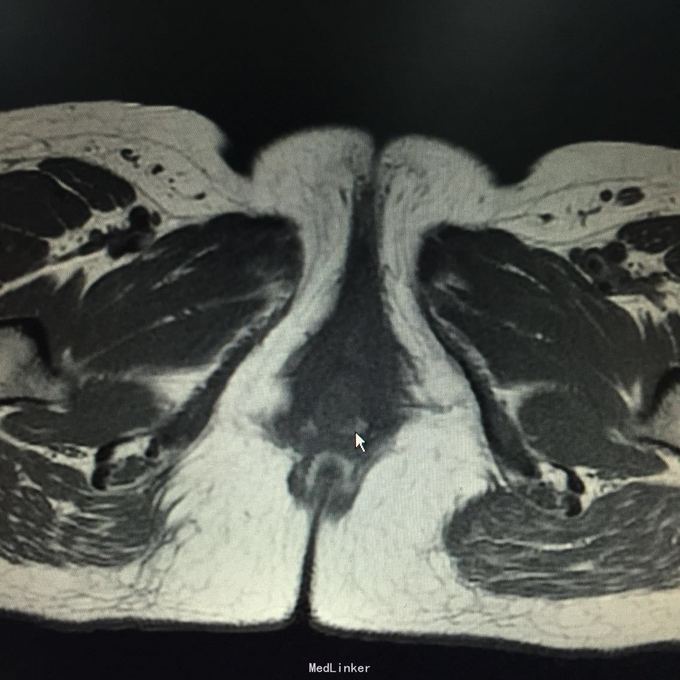

查体:会阴部位可及一大小约3*2cm质硬肿物,边界清,无压痛。阴道残端愈合可。辅助检查:HPV-DNA、LCT未见异常,阴道镜检查:会阴肿物,性质待查。彩超体表肿物:阴道口左侧低回声团,范围约42*20mm,肿块距体表1.8mm,内见丰富血流信号。盆腔MR:宫颈癌根治术后改变,阴道残端下份、阴道口占位,建议活检,双侧髂血管旁、腹股沟多发稍大淋巴结。会阴部位肿物。彩超:子宫切除术后,盆腔未见明显占位,肝胆胰脾双肾输尿管膀胱未见异常。